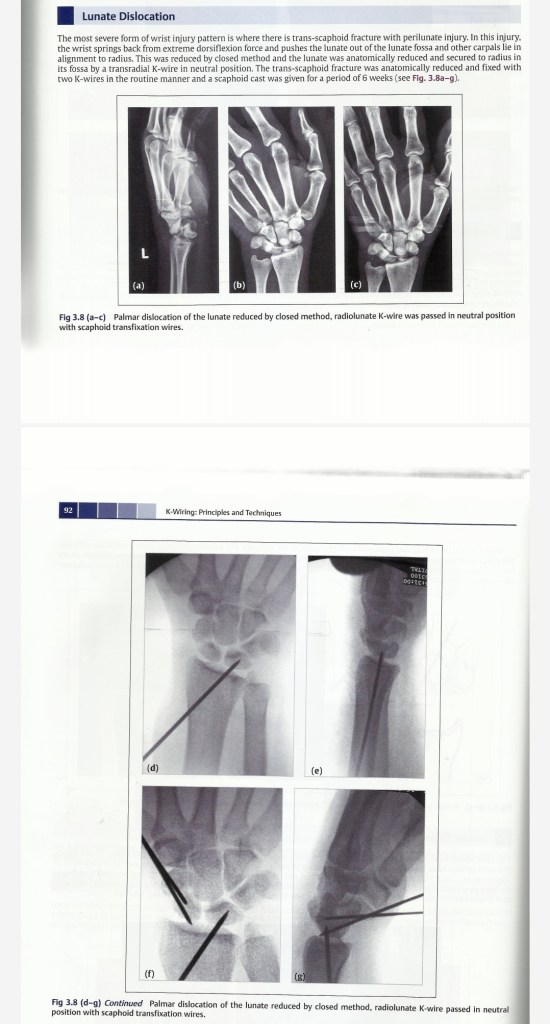

Lecture Wrist dislocation & RUJ dislocation